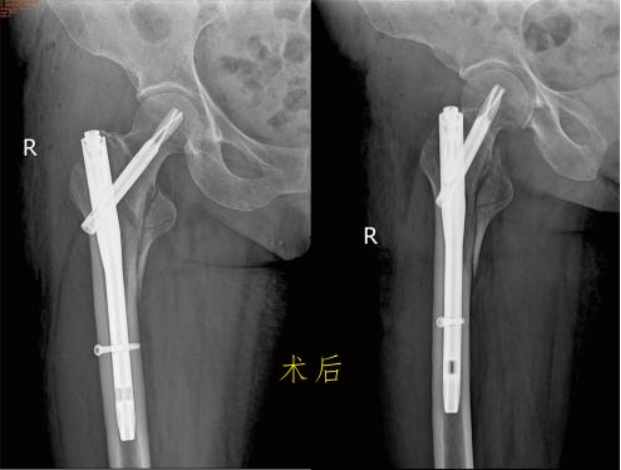

保守治疗 一般说的是卧床、牵引固定,等待骨折自己愈合。费用看似低廉,不用开刀出血,感觉上好像很安全,但老年人由于年纪大、体质差、新陈代谢水平低等原因,发生骨折后的愈合时间较长,所以保守治疗的缺点更多: 2.卧床时间长:髋部由于位置特殊,不像上肢骨折一样可以夹板石膏固定而不影响日常活动,一般髋部骨折通常要床边牵引制动2~3个月甚至更长,吃喝拉撒都在床上。看似很安稳,其实对于患者来说很痛苦。 3.并发症多:长期卧床容易产生褥疮;坠积性肺炎。泌尿系感染、深静脉血栓形成等,严重者危及生命。 4.治疗效果欠佳:单纯的牵引治疗很难保证复位质量。多数患者的骨折容易畸形愈合甚至不愈合,下肢短缩跛行,影响以后的生活质量。 5.加重骨质疏松:长期卧床、制动、骨量大量丢失,使原本的骨质疏松更加雪上加霜。 手术治疗 股骨颈骨折根据骨折移位情况,患者身体状况、年龄、预期寿命等因素,选择空心钉内固定术、人工半髋关节置换术或全髋关节置换术。股骨粗隆间骨折,一般采用闭合复位防旋髓内针内固定术或人工髋关节置换术。股骨粗隆下骨折主要是切开复位髓内针内固定术,很少使用钢板内固定术。 虽然老年髋部骨折术后死亡率高,国内外对其治疗方式争论不断,但研究表明。手术在降低死亡率、并发症发生率方面有明显优势。选择合适手术方式治疗老年髋部骨折可有效的降低死亡率、并发症发生率、改善患者生存质量。真正提高他们的生活质量。 更有多个研究发现,老年髋关节周围骨折的病人采取保守治疗之后的一年内死亡率接近50%!长期卧床引起的并发症,不管是褥疮、血栓、坠积性肺炎还是各种感染,都有可能会是致命的,这才是导致患者死亡的根本原因。 对此我们建议:在符合手术指征的前提下,老年髋部骨折应优选手术治疗。 九江市第一人民医院开发区分院/朱挺平